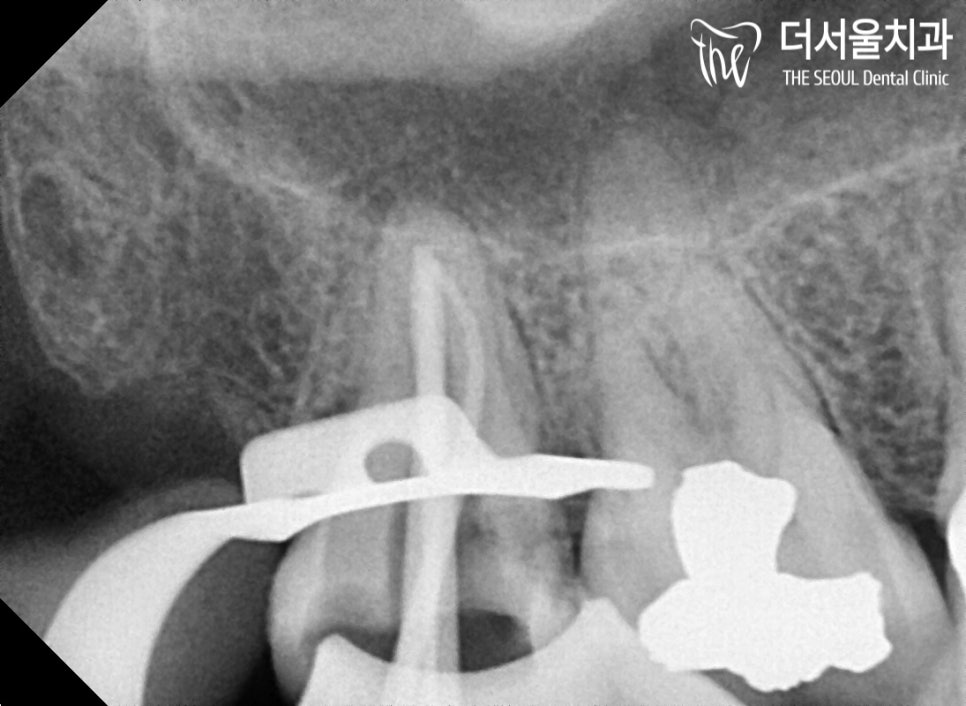

『신경치료 를 통한 증상 완화』

이런 말 하기 쑥스럽지만,

임플란트는 물론이며

신경치료 도 잘~하는 더 서울입니다.

그러니 너무 걱정하지 않으셔도 됩니다^^

클램프와 러버댐, 필수인 거 아시죠?

방습 환경을 철저하게 지키며

근관 제거, 소독, 충전 과정을 거쳤습니다.

충치가 생각보다 깊게 진행되어 있었는데요.

혹시나 병소가 남아있진 않을까

수차례 확인을 거쳤습니다.